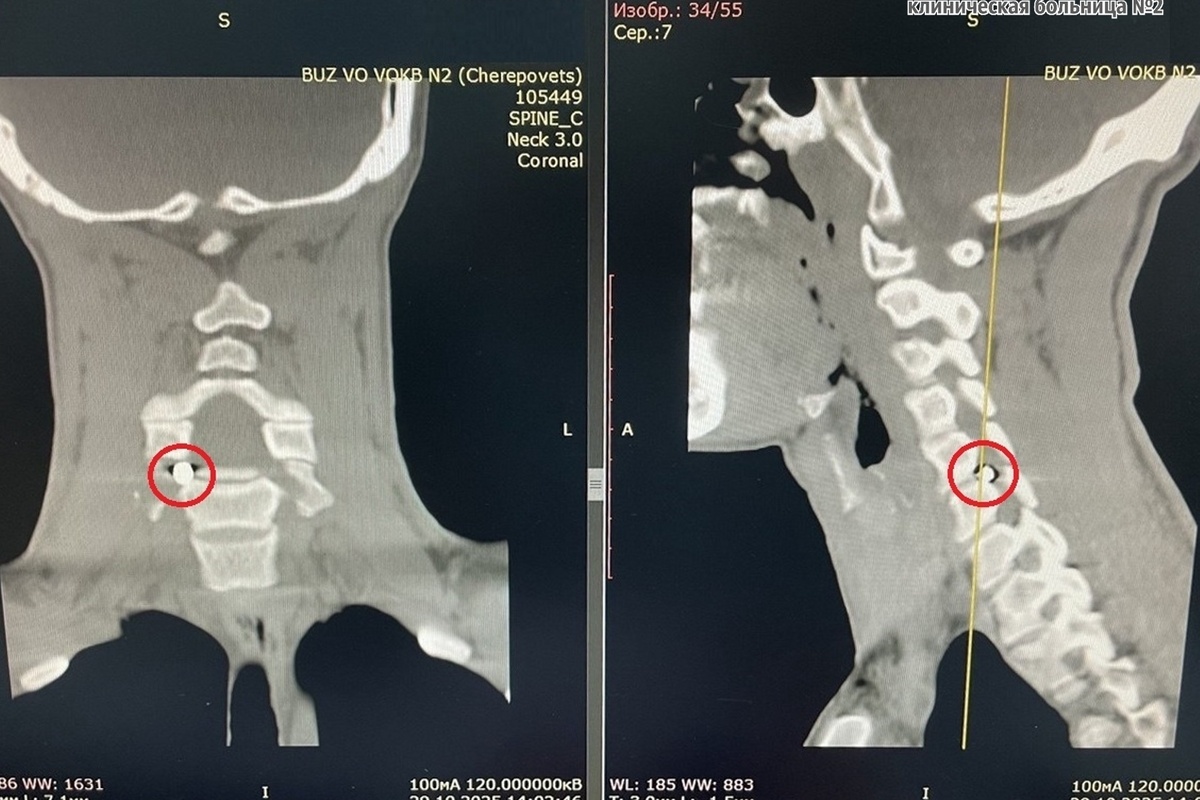

Компьютерная томография показала инородное тело в шейном отделе позвоночника. Осколок снаряда пять на четыре миллиметра застрял в позвоночном канале и сдавливал спинномозговой корешок. При любом движении он вызывал острую боль в шее, отдающую в руку, онемение и слабость в кисти.

️Осколок находился рядом с позвоночной артерией. В других больницах оперировать не брались. В больнице № 2 решили провести гибридную операцию с участием специалистов разных профилей.